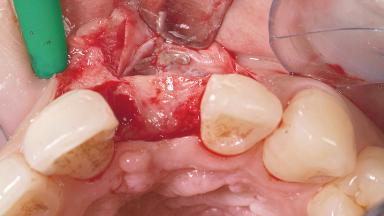

A 30-year-old female patient had lost tooth 21 and was referred to our clinic for consultation and treatment. Due to advanced apical infection, tooth 21 had been extracted two months earlier at another clinic and an acrylic-resin tooth had been bonded to the adjacent teeth. The patient desired implant treatment to avoid any damage to the adjacent natural teeth. While the patient had no history of any systemic disorder, she was a heavy smoker and exhibited medium to advanced periodontitis in the entire jaw. After the initial treatment to achieve a pocket probing depth of less than 4 mm and no bleeding on probing, a decrease in the height of the papillae mesial and distal to the extraction site and overall gingival recession were observed.

Bone Augmentation | Horizontal|Staged |

Augmentation Materials | Autogenous chips|Membrane |

Soft Tissue Grafting | Simultaneous |